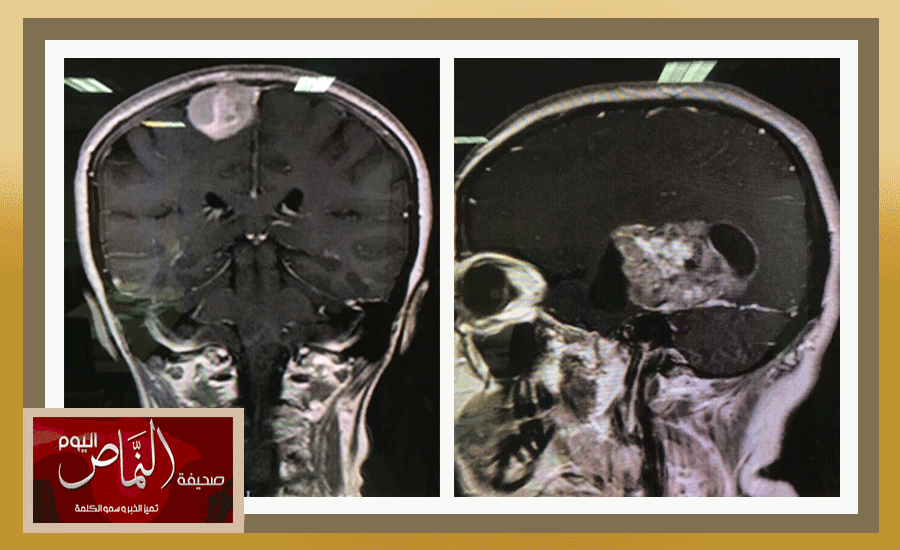

في إنجاز نوعي، أجرى قسم جراحة المخ والأعصاب بمستشفى عسير 3 عمليات كبرى لأورام دماغية من فئات متعددة، عانت من أمراض مختلفة، وذلك بقيادة رئيس القسم الاستشاري الدكتور عوض الشهري. وأكد الشهري أن هذا الرقم النوعي من إجراء العمليات في مدة وجيزة يؤكد كفاءة القسم وكادره الطبي، مشيرًا إلى أن مستشفى عسير هو المستشفى المركزي للمنطقة الجنوبية والذي يقوم بكافة عمليات جراحة المخ والأعصاب والعمود الفقري. وامتدح الشهري التعاون اللامحدود بين الأقسام في المستشفى، خصوصًا قسم العناية المركزة لتقديم الخدمات الفائقة ما بعد العمليات الجراحية، وكذلك قسم التخدير، في ظل الدعم من المشرف العام على المستشفى أحمد الهيزعي، مشددًا على أن المستشفى يواصل تقديم الخدمات وتطوره المستمر في شتى الجوانب.